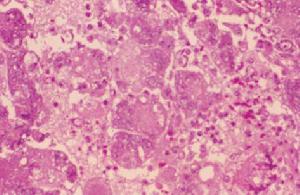

喉痛、聲嘶、喉喘鳴和呼吸困難,並可伴發熱惡寒,咽喉疼痛,喉鏡下可見黏膜呈深紅色水腫、表面發亮,喘鳴,聲嘶,呼吸困難,甚則窒息,喉鏡下可見喉黏膜瀰漫性水腫,蒼白。